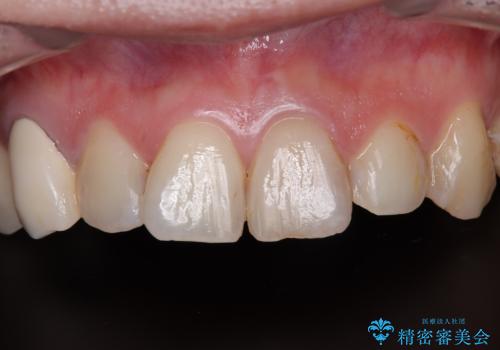

変色と捻れた前歯 オールセラミッククラウン補綴治療

- むし歯により神経を取り除く処置をした歯と隣接する歯の捻れを気にして来院された患者様です。

神経を取り除いた歯は変色が始まっており、隣の歯は捻れにより突出している印象であったので、前歯2歯をオールセラミッククラウンにて補綴することとしました。